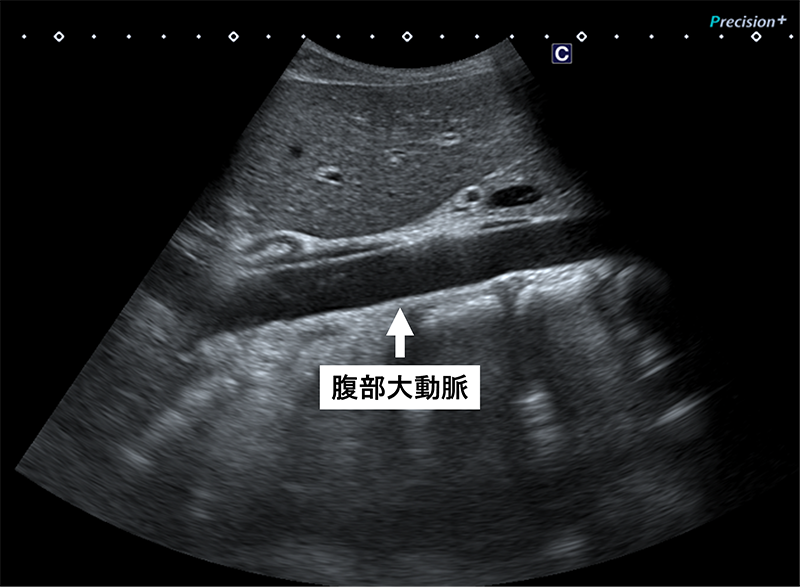

腹部大動脈

- 腹部大動脈瘤の有無

- 動脈硬化性変化の有無

※ 腹部大動脈瘤は自覚症状が出にくく、高血圧・喫煙歴・高齢の方では特にエコー評価が有用です。